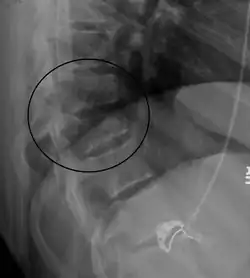

| A Chance fracture of T10 and fracture of T9 due to a seatbelt during an MVC. | |

| Diagnostic method | Medical imaging (X-ray, CT scan)[1] |

A Chance fracture is a type of vertebral fracture that results from excessive flexion of the spine.[8][9] Symptoms may include abdominal bruising (seat belt sign), or less commonly paralysis of the legs.[4][10] In around half of cases there is an associated abdominal injury such as a splenic rupture, small bowel injury, pancreatic injury, or mesenteric tear.[3][5] Injury to the bowel may not be apparent on the first day.[11]

The cause is classically a head-on motor vehicle collision in which the affected person is wearing only a lap belt.[2] Being hit in the abdomen with an object like a tree or a fall may also result in this fracture pattern.[12][10] It often involves disruption of all three columns of the vertebral body (anterior, middle, and posterior).[7][6] The most common area affected is the lower thoracic and upper lumbar spine.[6] A CT scan is recommended as part of the diagnostic work-up to detect any potential abdominal injuries.[5] The fracture is often unstable.[1]

On plain X-ray, a Chance fracture may be suspected if two spinous processes are excessively far apart.[10]